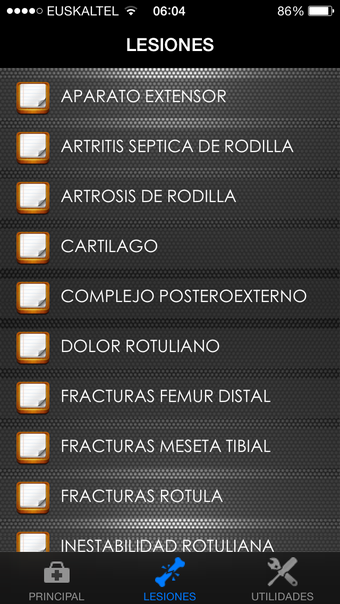

Rodilla App is a free program for Android, that belongs to the category 'Medical'.About Rodilla App for Android

Rodilla App requires Android 9.0 and above. The current version of the program is 7.0.0, and you can run it in English, Spanish and German.